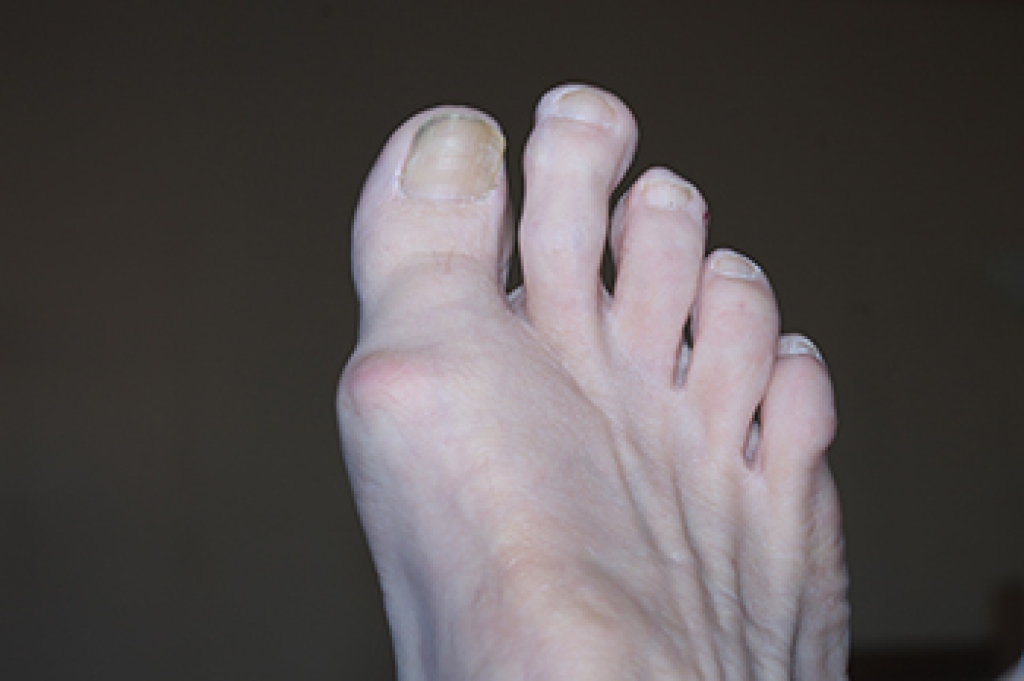

Painful Lumps on the Toes

Lumps on the toes can develop for several reasons and may vary in size, texture, and level of discomfort. Some lumps grow slowly over time while others appear suddenly after irritation or injury. A common cause is a bunion or bunionette, which forms when the toes shift and creates a bony bump. Ganglion cysts may also appear near the joints or tendons and feel like soft, fluid-filled swellings under the skin. Corns and callouses can sometimes look like small lumps because the skin thickens in response to pressure from shoes. In some cases, a lump may develop from arthritis in the toe joint, which can create bony enlargements that feel firm and tender. Other possibilities include gout deposits, small benign growths, or inflammation of the surrounding tissues. A podiatrist can examine the toe and may use imaging to determine the exact cause of the lump. Treatment depends on the diagnosis and may include footwear changes, padding, medication, or other corrective care. If you notice a lump on your toe, it is suggested that you make an appointment with a podiatrist.

- Bunions